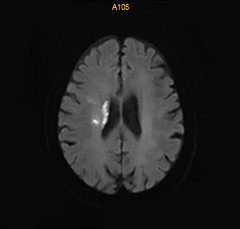

术后DWI:磁共振见少许新鲜脑梗死。

什么叫桡鞘【例久弥新】寻道于桡——瑞康通5.5F IntroSky X导管鞘经桡动脉行右侧大脑中动脉取栓一例_https://www.jmylbn.com_新闻资讯_第28张